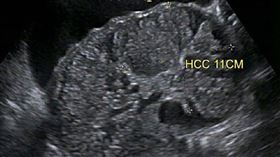

40歲男以為脹氣!超音波一掃巨大肝腫瘤

一名40歲男性近日因腹部脹大、感覺不適前往門診就醫,...